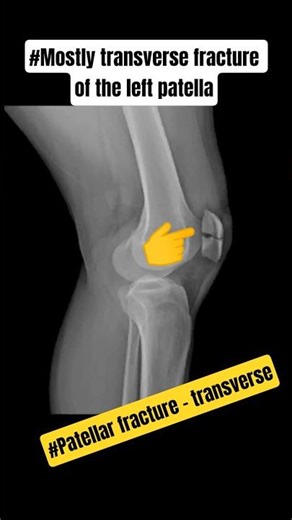

Mostly transverse fracture of the left patella#shortvideo

RadiotechAnoop